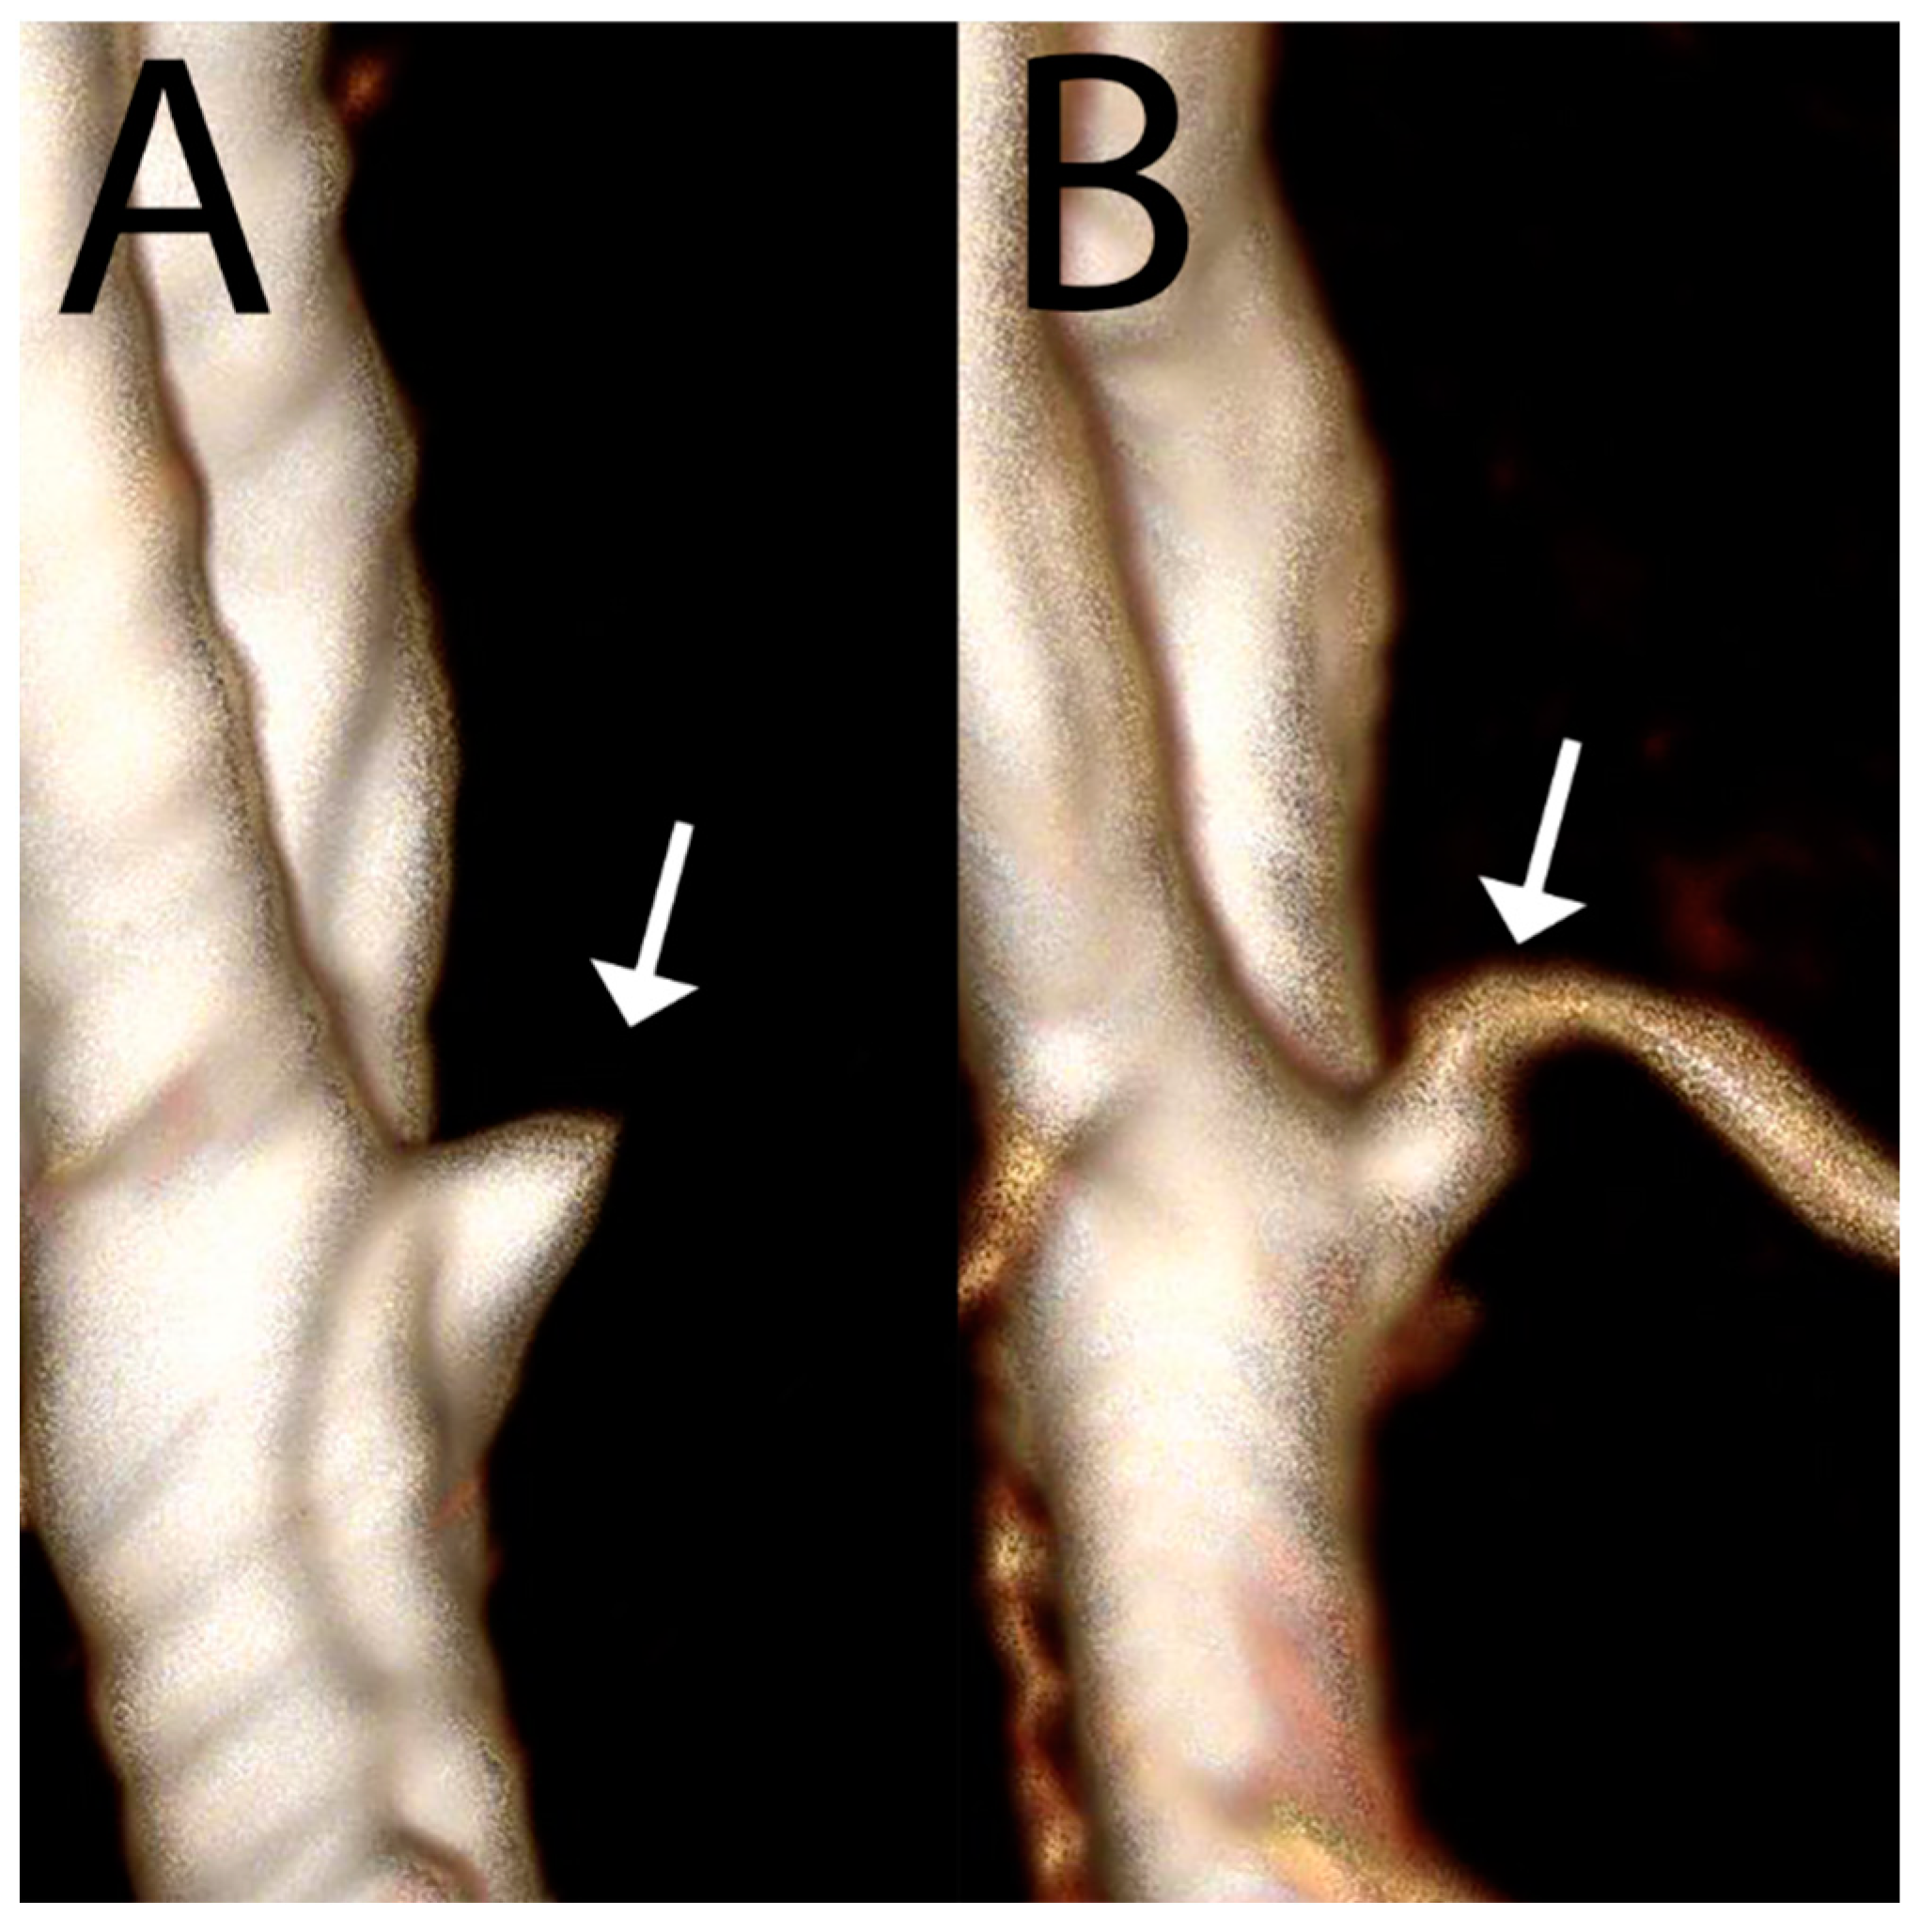

- Wermer, M.J.; van Walderveen, M.A.; Garpebring, A.; van Osch, M.J.; Versluis, M.J. 7 Tesla MRA for the differentiation between intracranial aneurysms and infundibula. Magn. Reson. Imaging 2017, 37, 16–20. [Google Scholar] [CrossRef] [PubMed]

- Özütemiz, C.; White, M.; Elvendahl, W.; Eryaman, Y.; Marjańska, M.; Metzger, G.J.; Patriat, R.; Kulesa, J.; Harel, N.; Watanabe, Y.; et al. Use of a Commercial 7-T MRI Scanner for Clinical Brain Imaging: Indications, Protocols, Challenges, and Solutions—A Single-Center Experience. Am. J. Roentgenol. 2023, 221, 788–804. [Google Scholar] [CrossRef]